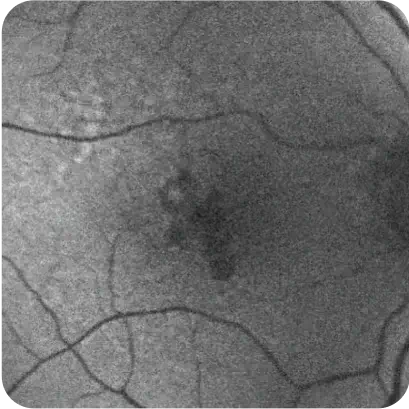

What may be happening to the retina and your patient's vision7

What may be happening to the retina

What may be happening to your patient's vision7

Some loss of peripheral, low‑light vision

Representation of vision loss for illustrative purposes only.

Images courtesy of Heidelberg Engineering, Dr. Julie Rodman, and Dr. Mohammad Rafieetary.